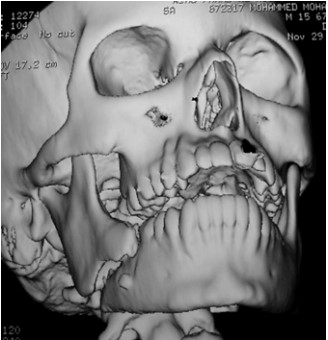

The medical records and panoramic radiographs, C.T and 3D C.T (figures 1-4) of 50 patients with mandibular angle fractures were examined. The presence and absence and degree of impaction of the lower third molar were assessed for each patient and related to the occurrence of fracture of the mandibular angle in addition to evaluate the degree of displacement of the fracture.

Fig 3: Panoramic radiograph of angle fracture associated with third molar.

The incidence of mandibular angle fracture was found to be greater when a lower third molar was present. Patients exhibiting angle fractures associated with third molar represented 74 % of all angle fractures in this investigation.

In this study, mandibular angle fracture associated with lower third molar represented 74 % of all cases and this result provided an evidence that third molar tooth represents a weak point of the mandible that lowers the resistance of the bone to fracture. This result is in agreement with the result of researches of Lee et al ,Ugboko et al ,Joyce et al, Kim and Linda et al (10-14) .